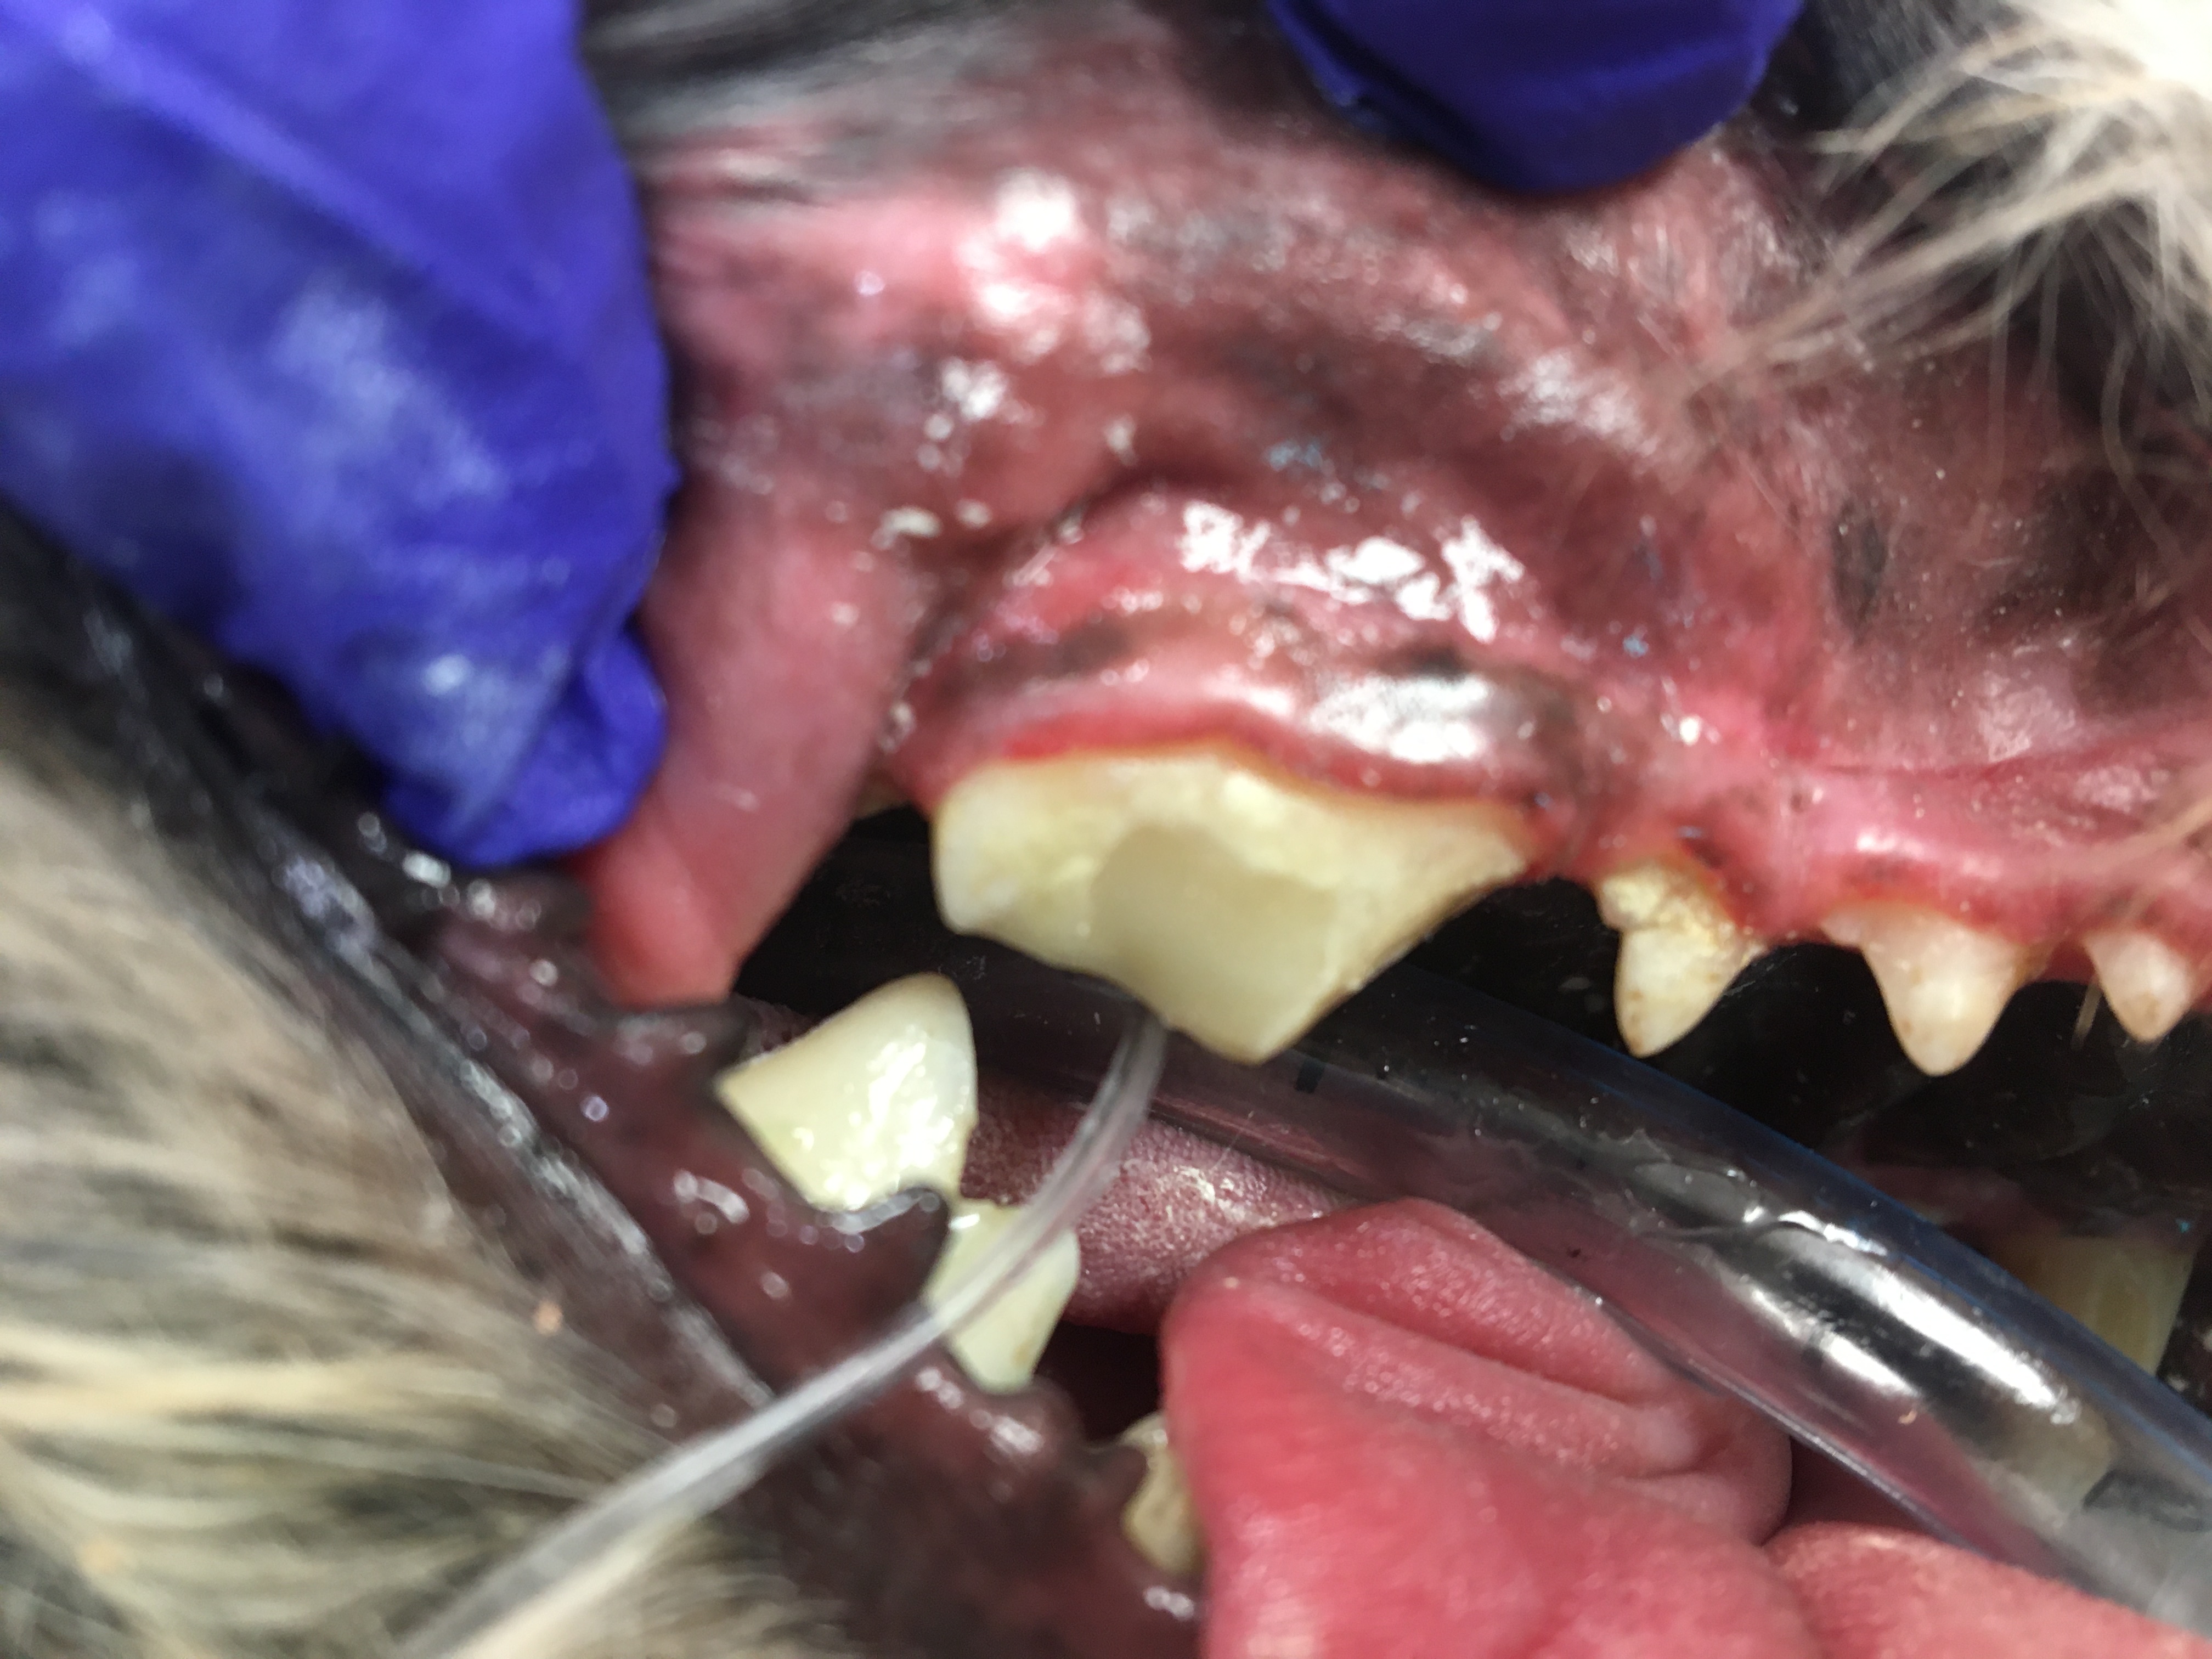

Feline Odontoclastic Resorptive Lesions

Felines exhibit a unique erosion at the cervical area called Feline Odontic Resorptive Lesions. These lesions appear to be associated with localized gingivitis. Many people have tried to explain why these lesions develop, however no one has come up with a definitive etiology.

I have restored FORL lesions with silver amalgam with excellent long term effect in multiple feline species. The lesions have ceased to enlarge. Restoration attempts with composite resin will fail, erosion will continue. Regrettably, most dentists and veterinary dentists will no longer have silver amalgam and the necessary instruments available to use it.

In personal conversations with Dr. Thomas Clark at Louisville Zoo I learned that he also has had success with silver amalgam. The lesion must be prepared with inverted cone burs to establish mechanical retention. These restorations have held up without failure for many years, see photos.